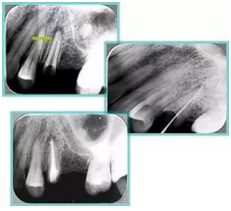

共有 4 張 X 線片,分別是術(shù)前、診斷絲 、主牙膠尖確認(rèn)、術(shù)后。

( 1 )術(shù)前:術(shù)前 X 線片用來了解牙齒的大概情況。術(shù)前預(yù)期為多根牙時 X 線片應(yīng)偏頭拍攝。

( 2 )診斷絲:根據(jù)術(shù)前 X 線片進(jìn)行開髓、根管的初步預(yù)備后,需要插入診斷絲,用來指示工作器械位置。常用 10 號或 15 號擴(kuò)大器作為診斷絲插入牙髓腔。

( 3 )主牙膠尖確認(rèn):通過術(shù)前預(yù)期和診斷絲診斷,明確工作長度、牙根走向,進(jìn)行根管預(yù)備。之后應(yīng)進(jìn)行主牙膠尖(中銼)確認(rèn),已明確根管是否適合充填。

( 4 )術(shù)后:觀察治療效果。